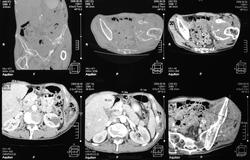

Здесь представлены КТ срезы брюшной полости и таза с контрастированием, выполненные через 2 года после травмы.

Артериальная фаза

Венозная фаза

на серии кт определяются в средней трети левой почки ,латерально от ее ворот определяется гиповаскулярный участок с четкими ровными контурами .с поддавливанием чашечно-лоханочной системы,ограниченый капсулой почки ,неправильной вытянутой формы ,который в поздней венозной фазе не изменяет своей визуализации (д.д между кистой и кистозной формой почечно-клеточного рака).латерально от левой почки в мягких тканях определяется большой участок со сниженной денситометрической плотностью,размерами - 53х117мм ,с включениями газа и кольцом периферического усиления,с дренажом(вероятнее всего крупный абсцесс).печень увеличена в размере,селезенка с включениями кальция .размеры поджелудочной железы в пределах нормы,холедох и вирсунгов проток без патологии.надпочечники нормальных размеров,без изменений.в области левого тазобедреного сустава определяется участок деструкции с разрушением вертлужной впадины ,головки и шейки бедренной кости ,смещением повздошной кости вверх и латерально на 111.1мм,с фрагментом головки левой бедренной кости .в левой повздошной кости определяются гиперостоз с обширным участком остеосклероза и мелкими участками остеолитической деструкции (смешанный тип).аналогичные остеолитические изменения в крыле правой повздошной кости и в головке правой бедренной кости (сужу по 3d).по медиальному контуру средней трети тела поздошной кости определяется разрушение замыкательной пластинки с вовлечением губчатого вещества на большом протяжении,в крыше и самой вертлужной впадине с мягкотканным компонентом ,с участками пониженной денситометричской плотности (вероятнее всего участки некроза),с мелкими костными фрагментами (что косвенно может подтверждать рост изнутри снаружу),с поддавливанием на большом протяжении органов малого таза,латерально -левая стенка мочевого пузыря утолщена.вывод :такие изменения могут быть как первичного так и метастатического характера .первопричина протрузии возможно врожденного характера(дисплазия) ,затем перелом усугубил процесс(посттравматическая протрузия).меня настораживает тот момент,что изменения в повздошной кости напоминают хронический остемиелит изначально .а затем появились изменения ,сильно напоминающие озлакочествление+изолированно крупный абсцесс